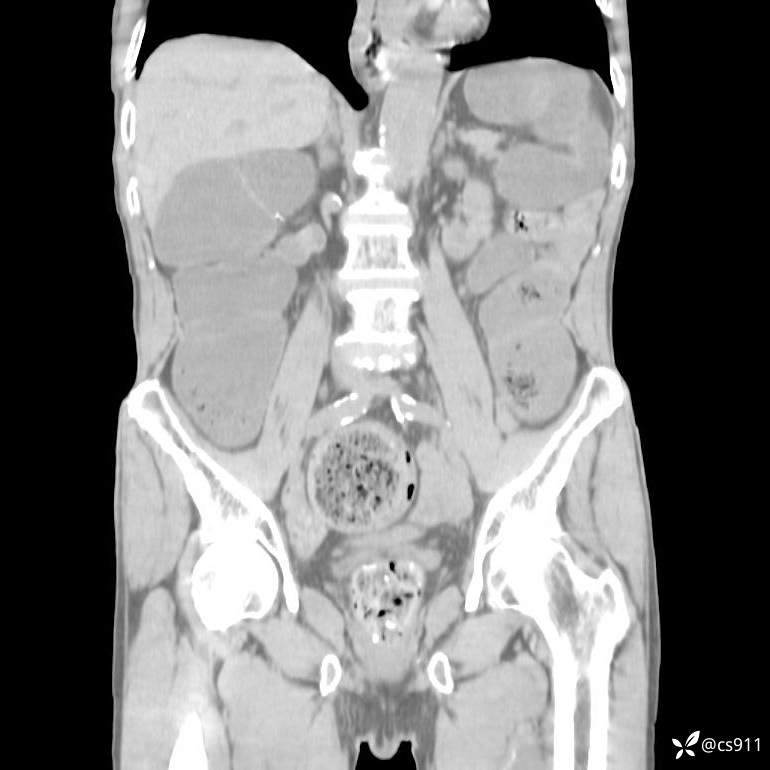

急腹症之急诊CT,原因?答案公布

男,77岁,腹痛、腹胀伴恶心呕吐1天。呕吐胃内容物,非喷射性呕吐,有咖啡色样胃内容物,诉有胃穿孔病史。查体:全腹平,下腹部压痛,全腹无反跳痛,叩诊呈浊音,移动性浊音阴性,肠鸣音减弱,1-2次/分。肛检:直肠未扪及明显肿物,可触及大量粪块。

T 36.6℃ P 80次/分 R 26次/分 BP 100/60mmHg

白细胞(WBC) H 14.55 10e9/L 4-10

中性粒细胞百分率(NEUT%) H 85.7 % 40-75

血淀粉酶(AMY) HH 1859 U/L 35-135

癌胚抗原(CEA) H 27.44 ng/ml 0-5

呕吐物 潜血试验 * 阳性 阴性

患者轮椅入室检查神志清楚, 能配合摆位和呼吸